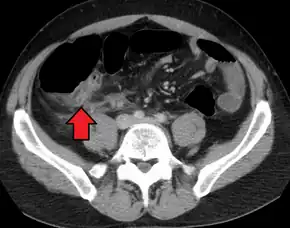

In children the clinical examination is important to determine which children with abdominal pain should receive immediate surgical consultation and which should receive diagnostic imaging.[42] Because of the health risks of exposing children to radiation, ultrasound is the preferred first choice with CT scan being a legitimate follow-up if the ultrasound is inconclusive.[43][44][45] CT scan is more accurate than ultrasound for the diagnosis of appendicitis in adults and adolescents. CT scan has a sensitivity of 94%, specificity of 95%. Ultrasonography had an overall sensitivity of 86%, a specificity of 81%.[46]

Computed tomography

Where it is readily available, computed tomography (CT) has become frequently used, especially in people whose diagnosis is not obvious on history and physical examination. Although some concerns about interpretation are identified, a 2019 Cochrane review found that sensitivity and specificity of CT for the diagnosis of acute appendicitis in adults was high.[51] Concerns about radiation tend to limit use of CT in pregnant women and children, especially with the increasingly widespread usage of MRI.[52][53]

The accurate diagnosis of appendicitis is multi-tiered, with the size of the appendix having the strongest positive predictive value, while indirect features can either increase or decrease sensitivity and specificity. A size of over 6 mm is both 95% sensitive and specific for appendicitis.[54]

However, because the appendix can be filled with fecal material, causing intraluminal distention, this criterion has shown limited utility in more recent meta-analyses.[55] This is as opposed to ultrasound, in which the wall of the appendix can be more easily distinguished from intraluminal feces. In such scenarios, ancillary features such as increased wall enhancement as compared to adjacent bowel and inflammation of the surrounding fat, or fat stranding, can be supportive of the diagnosis. However, their absence does not preclude it. In severe cases with perforation, an adjacent phlegmon or abscess can be seen. Dense fluid layering in the pelvis can also result, related to either pus or enteric spillage. When patients are thin or younger, the relative absence of fat can make the appendix and surrounding fat stranding difficult to see.[55]